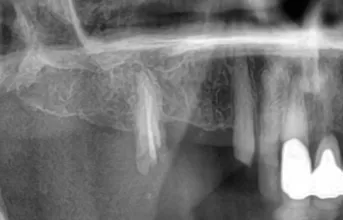

Direktimplantat efter tandutdragning – ett kliniskt exempel på när det lönar sig att vänta Direktimplantat efter tandutdragning är en behandlingsmetod som innebär att ett tandimplantat placeras direkt i alveolen efter att en tand tagits bort. När det används korrekt kan det ge mycket goda resultat med kortare behandlingstid och färre kirurgiska ingrepp. Men som med […]

Sinuslyft och Tandimplantat – Så Återställde Vi Benvolymen för en Stabil Implantatbehandling

Läs hur vi med hjälp av sinuslyft och benmaterial kunde möjliggöra stabil implantatbehandling i överkäken trots benbrist.